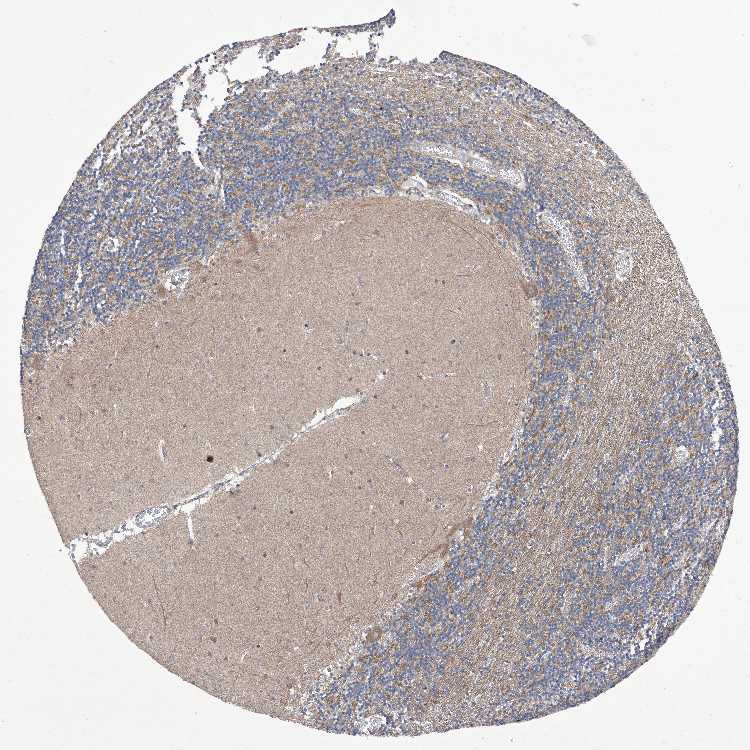

CEREBELLUM - Antibody stainingi

Antibody staining in the annotated cell types in the current human tissue is reported as not detected, low, medium, or high, based on conventional immunohistochemistry profiling in selected tissues. This score is based on the combination of the staining intensity and fraction of stained cells.

Each image is clickable and will lead to virtual microscopy that enables deeper exploration of all samples and also displays staining intensity scores, fraction scores and subcellular localization as well as patient and tissue information for each sample.

Antibody HPA031204Antibody HPA031205

Purkinje cells HighMedium

Cells in granular layer MediumMedium

Cells in molecular layer LowNot detected